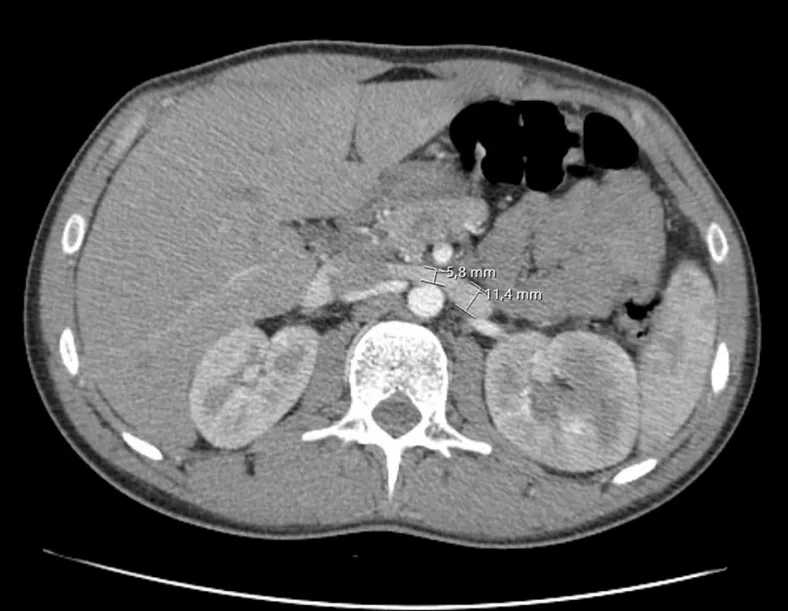

Diante de quadro de lombalgia e hematúria, foi realizado TC de abdome que evidenciou compressão da veia renal esquerda entre a artéria mesentérica superior e a aorta.

É possível observar a redução de calibre na veia renal que está passando entre aorta e artéria mesentérica superior.

Olha que imagem interessante, redução do ângulo entre artéria mesentérica e aorta com compressão da veia renal.

Diagnóstico: Síndrome do quebra-nozes (Nutcracker Syndrome)

O fenômeno do quebra-nozes, também conhecido como síndrome de aprisionamento da veia renal esquerda (VRE), refere-se à compressão da VRE mais comumente entre a aorta abdominal e a artéria mesentérica superior. O termo síndrome do quebra-nozes é usado para pacientes com sintomas clínicos associados à anatomia do quebra-nozes. Os sintomas variam desde hematúria assintomática até congestão pélvica grave. O manejo da síndrome depende da apresentação clínica e da gravidade da hipertensão da VRE. O diagnóstico é difícil e exige a exclusão de outras causas mais comuns. A confirmação do diagnóstico requer exames de imagem.